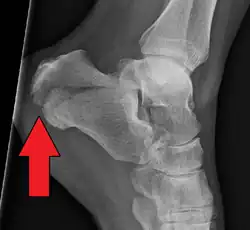

A calcaneal fracture is a break of the calcaneus (heel bone).[1] Symptoms may include pain, bruising, trouble walking, and deformity of the heel.[1] It may be associated with breaks of the hip or back.[1]

It usually occurs when a person lands on their feet following a fall from a height or during a motor vehicle collision.[2][1] Diagnosis is suspected based on symptoms and confirmed by X-rays or CT scanning.[1]

Conventional radiography is usually the initial assessment tool when a calcaneal fracture is suspected. Recommended x-ray views are (a) axial, (b) anteroposterior, (c) oblique and (d) views with dorsiflexion and internal rotation of the foot. However, conventional radiography is limited for visualization of calcaneal anatomy, especially at the subtalar joint. A CT scan is currently the imaging study of choice for evaluating calcaneal injury and has substituted conventional radiography in the classification of calcaneal fractures.[13] Axial and coronal views are obtained for proper visualization of the calcaneus, subtalar, calcaneocuboid and talonavicular joints.

The Angle of Gissane, or "Critical Angle", is the angle formed by the downward and upward slopes of the calcaneal superior surface. On a lateral radiograph, an angle of Gissane > 130° suggests fracture of the posterior subtalar joint surface. Böhler's angle, or the "Tuber Angle", is another normal anatomic landmark seen in lateral radiographs. It is formed by the intersection of 1) a line from the highest point of the posterior articular facet to the highest point of the posterior tuberosity, and 2) a line from the former to the highest point on the anterior articular facet. Böhler's angle is normally 25° to 40°.[14] It is named after Austrian physician Lorenz Böhler.[16] A decreased angle is indicative of a calcaneal fracture.